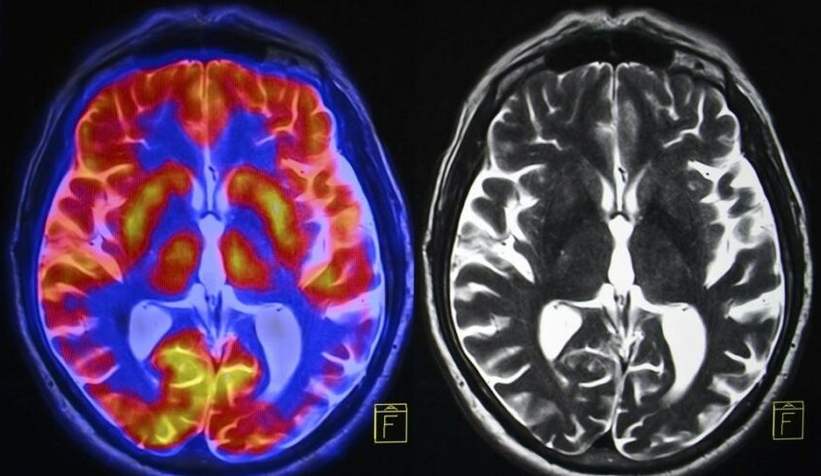

Litvanya’nın saygın eğitim kurumlarından Kaunas Teknik Üniversitesi’nde görevli bilim insanları yapay zeka ile Alzheimer’ı erken teşhis edebilen bir beyin tarama sistemi geliştirildiğini duyurdu.

Yapılan açıklamada yeni teknolojinin Alzheimer’ı yüzde 99 oranında erken teşhis edebildiği belirtildi. Yeni bir yapay zeka ve derin öğrenme teknolojisi ile birlikte beyin taramalarında başarıya ulaşıldığı kaydedildi.